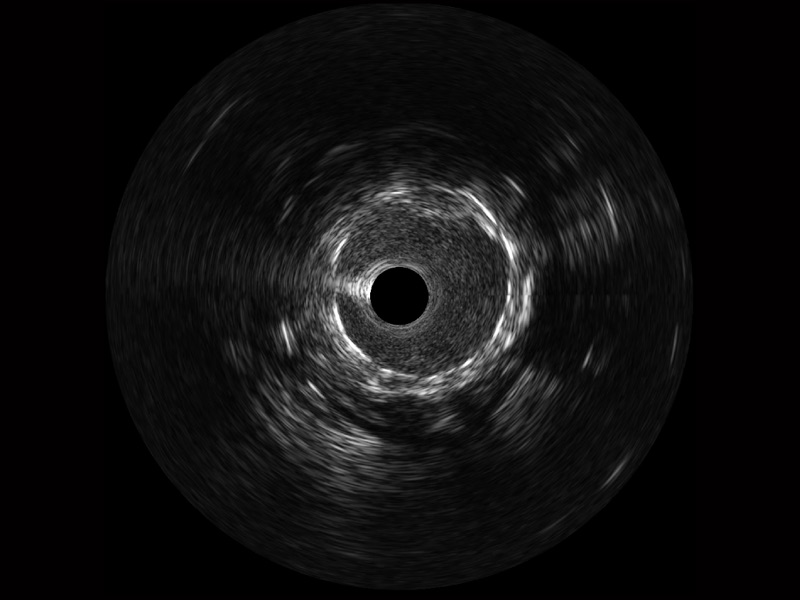

传统IVUS图像

对比传统IVUS导管成像,球速体育入口宽频IVUS图像的近场支架梁显影更细腻,远场中膜外血管仍清晰可辨,兼顾远中近,兼顾分辨力与穿透深度